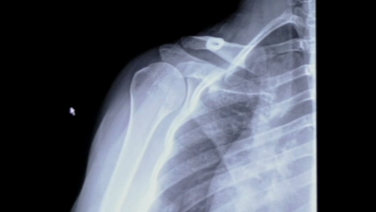

MR Arthrogram & Xray Review for a Labral Tear with Stephanie Muh, MD

Surgeon's Approach to Reading an MRI with Stephanie Muh, MD